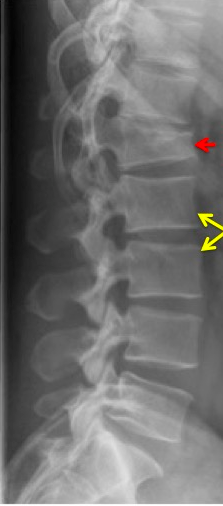

Identify the vertebral fracture(s)

How are vertebral fractures identified on X-ray?

loss in vertebral body height relative to normal adjacent vertebra or relative to